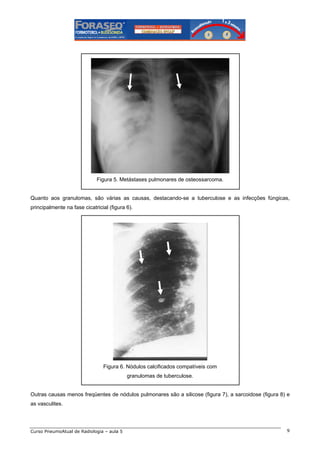

Figura 5. Metástases pulmonares de osteossarcoma.

Quanto aos granulomas, são várias as causas, destacando-se a tuberculose e as infecções fúngicas,

principalmente na fase cicatricial (figura 6).

Figura 6. Nódulos calcificados compatíveis com

granulomas de tuberculose.

Outras causas menos freqüentes de nódulos pulmonares são a silicose (figura 7), a sarcoidose (figura 8) e

as vasculites.